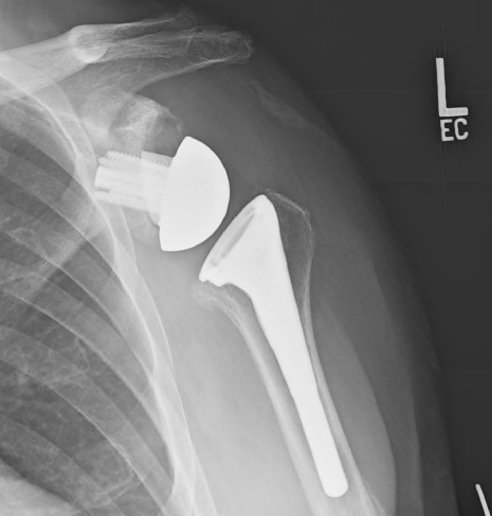

The shoulder joint (glenohumeral joint) is still being replaced as it would be in an anatomic total shoulder arthroplasty; however, instead of retaining the normal anatomic relationship of the ball-and-socket, the R-TSA switches/”reverses” the ball and the socket.

In other words, the replacement ball (glenosphere) now will be fixated to your shoulder socket (glenoid) and the socket (cup/humeral stem component) will be placed into the arm bone (humerus).

• A baseplate is secured with screws (4-5 in total) into the glenoid (socket) and a hemispherical ball is secured to this (glenosphere).

• A humeral stem is potted into the canal of the humerus with a size based on your anatomy.

• A highly cross linked polyethylene cup is secured into the humeral stem and articulates with the glenosphere.

• The glenosphere (ball) is typically made of a cobalt-chromium alloy.

• The baseplate and humeral stem are typically made of a titatium alloy.